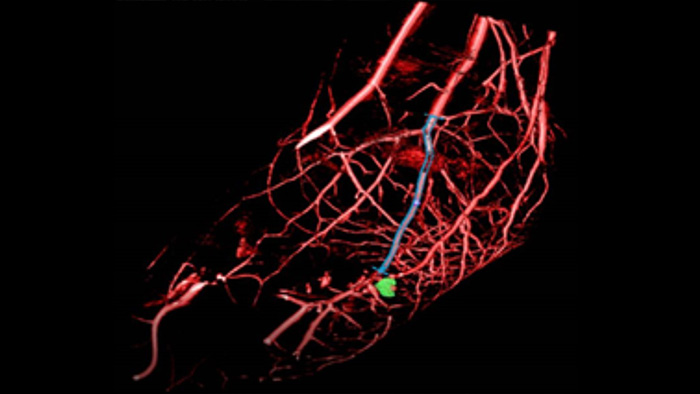

Diese Röntgen-Erfassungstechnik erzeugt eine vollständige, hochauflösende 3D-Darstellung der zerebralen, kardialen, abdominalen und peripheren Gefäße eines einzigen Rotationsangiographielaufs. Sämtliche Funktionen werden dabei über den Touchscreen am Tisch gesteuert. Dies kann die Sichtbarkeit stark gewundener oder komplexer Anatomien verbessern, die auf einem 2D- oder DSA-Bild möglicherweise nicht zu sehen sind.

SmartCT Vaso bietet 3D-Bildgebung mit hoher Auflösung, die wichtige zerebrovaskuläre Strukturen darstellt und so die räumliche Beurteilung von Gefäßen auf hohem Niveau unterstützt.

Die SmartCT Roadmap erleichtert komplexe Verfahren durch segmentierbare Live-3D-Bildführung, um das Zielgefäß sowie die Läsionen hervorzuheben und so die Navigation durch komplexe Gefäßstrukturen zu unterstützen. Sämtliche Funktionen werden über den Touchscreen am Tisch gesteuert.